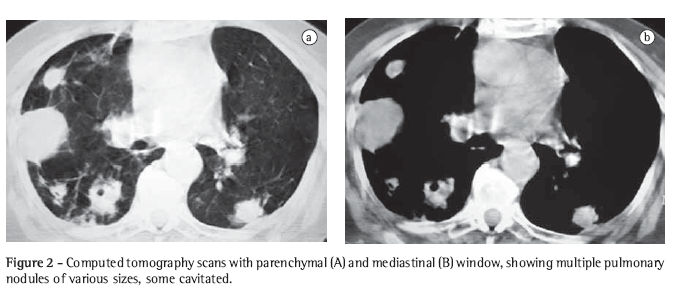

An 89-year-old white woman presented with COPD and bronchiectasis in the upper left lobe for 20 years. A functional diagnosis of COPD was made by calculating the ratio of the forced expiratory volume in one second/forced vital capacity, which was 41.2% after the use of bronchodilator in the pulmonary function test. She had been on daily use of tiotropium bromide, long-acting anticholinergics, associated with inhaled corticosteroid since September 2004; in acute exacerbations, she used systemic corticoids associated with broad spectrum antibiotics. She had presented cough with purulent sputum, 38°C fever, night sweats, severe prostration, dyspnea and anorexia for 5 days. A 10-day course of ciprofloxacin was prescribed, a treatment that resulted in no clinical improvement, and the patient was hospitalized for 10 days due to worsening of the clinical status. In this first admission, the chest X-ray showed thickening of the bronchial walls, small, ill-defined opacities in the right upper and lower lobes, as well as atelectasis with bronchiectasis in the left upper lobe. Klebsiella pneumoniae was isolated through sputum culture. Ceftriaxone, piperacillin and tazobactam were prescribed. The patient was discharged after improvement of the fever and cough. After discharge, there was recurrence of the symptoms, with worsening of the dyspnea. A chest X-ray was performed in the home, using a portable device. The X-ray showed disseminated nodules in the lungs, prompting a second hospitalization (Figure 1). Upon examination, the patient presented a general aspect of suffering: prostration; paleness; tachypnea (44 breaths/min); tachycardia (120 bpm); axillary temperature, 37°C; arterial pressure, 120/80 mmHg; peripheral oxygen saturation, 84% in room air. There were rhonchi in both lungs. The rest of the examination evidenced no alterations. Laboratory test results were as follows: 3,260,000 erythocytes/mm3; hematocrit, 28%; hemoglobin, 9.6 g/dL; 11,130 leukocytes/mm3; rods, 5%; segmented, 64%; eosinophils, 0%; lymphocytes, 10%; pH, 7.4; arterial oxygen tension, 68.7 mmHg; arterial carbon dioxide tension, 42.8 mmHg; peripheral oxygen saturation, 93%-with oxygen at 3 L/min using a nasal catheter; urea, 44.3 mg/dL; creatinine, 1.26 mg/dL; sodium, 135 mEq/L; and potassium, 5.4 mEq/L. The results of the liver function test, coagulation profile, echocardiogram and pelvic ultrasound were normal. Blood culture and serology were negative for HIV.

Initially, the association trimethoprim-sulfamethoxazole was prescribed, without clinical response. A 15-day course of amikacin, with imipenem and cilastatin, was then prescribed, resulting in an excellent clinical and radiological response (Figure 1). The patient was discharged with a prescription for an additional 8 weeks of trimethoprim-sulfamethoxazole.

The chest X-ray presentation of pulmonary nocardiosis is nonspecific. The most common radiological findings are consolidations and large irregular nodules. Nodules, cavitated masses, pleural effusion, pneumothorax, ground-glass opacities and interstitial patterns can occur as well.(1,4,5,11) Some studies show that, in HIV-infected patients, there is a higher percentage of cavitated lesions.(8) Alveolar consolidation in the upper lobes is often confused with pulmonary tuberculosis.(6) Although the alterations observed on CT scans are similar to those of the conventional X-rays, CT is superior in demonstrating the exact location and extent of the lesions, as well as in the differentiation between pulmonary and pleural lesions.(5) In the case reported, the patient presented nodules of various sizes, disseminated throughout both lungs, and some of those nodules were cavitated.